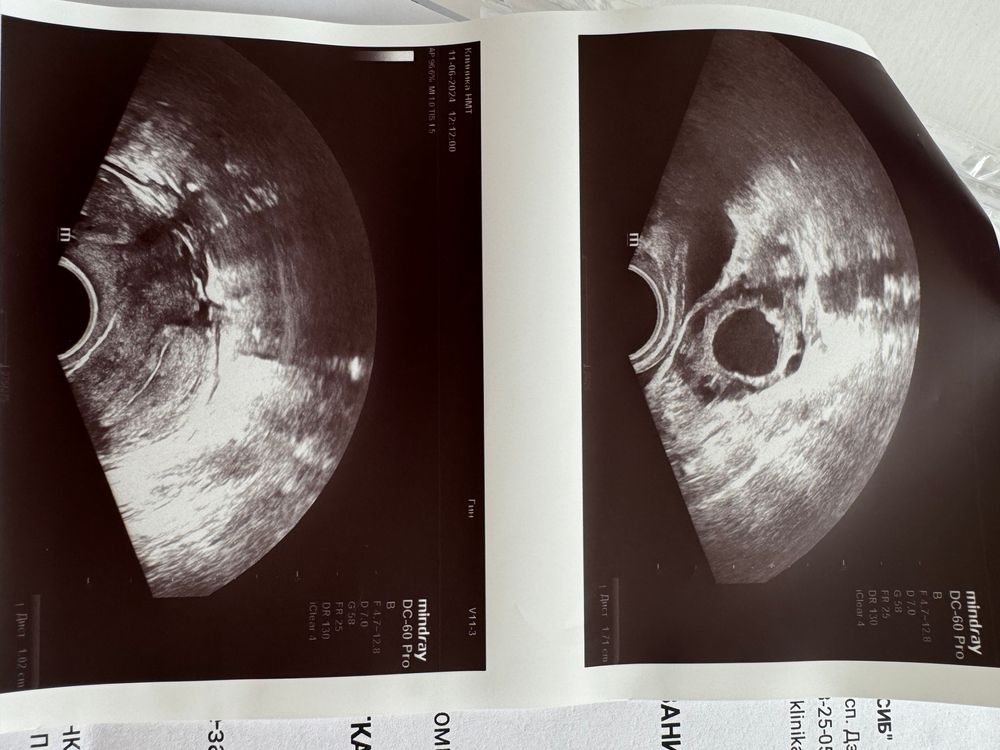

Это желтое тело работает, поэтому ноет. Если только не перепутали ДФ и ЖТ. Только почему-то жидкости нет, обычно она после О есть. А фото нет? На фото ДФ с четкими контурами и круглый, а жт расплывчатое.

Таня Орозова, вот фото Изображение

Алина, похож на фоллик

Кровоток не хороший , овуляция прошла примерно с 16-23, тут же еще цикл надо знать )